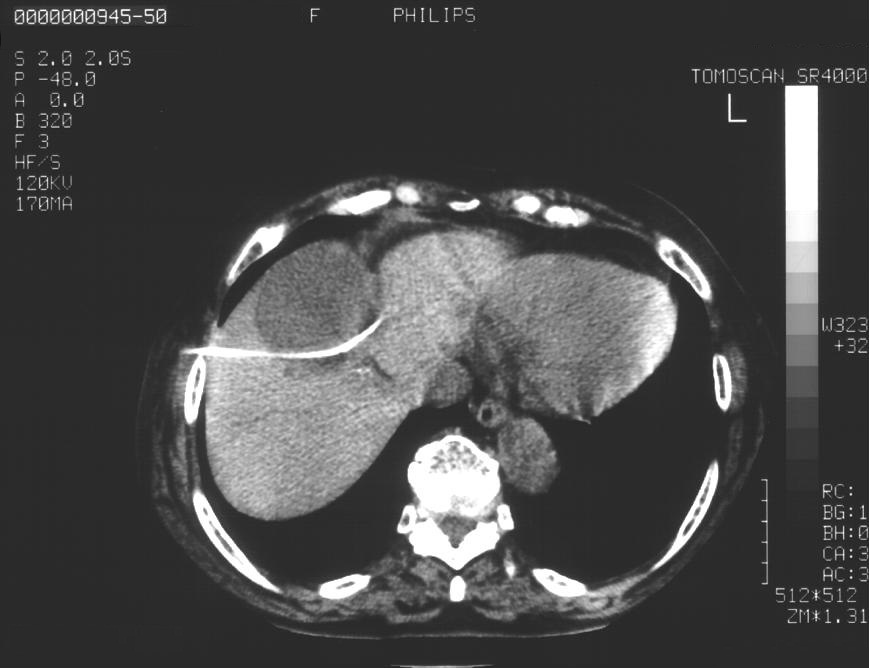

As a first step US or CT guided puncture of the lesion is performed with a correct needle size. (Figure 9.)

Image

Figure 9. – Hepatic cyst CT guided puncture (guide wire in the cyst)

After, a guide wire of 0,035” diameter is placed through the needle to the lesion, and the needle is removed. The guide wire is used to assist the insertion of a carefully selected, correct sized (6-14F) drainage catheter.